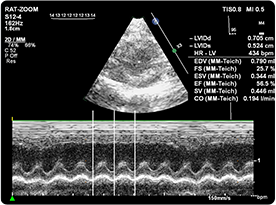

超聲成像技術(shù)是利用超聲波的物理特性和動物體器官組織聲學(xué)特性相互作用后產(chǎn)生的信息,經(jīng)信息處理形成圖像的成像技術(shù)。

動物體結(jié)構(gòu)對于超聲而言是一個(gè)復(fù)雜的介質(zhì),各種器官與組織(包括病理組織)都有它特定的聲像阻抗和衰減特性,因而構(gòu)成聲阻抗上的差別和衰減上的差異,這種不同的反射與衰減構(gòu)成了超聲圖像的基礎(chǔ)。因而根據(jù)顯示和記錄的波形、曲線或圖像的形式,借以進(jìn)行集體的檢查和疾病的診斷。

| 超聲儀(含氣麻費(fèi)用) | 450 | 元/只/次,單次5只起做 | 心超(射血分?jǐn)?shù)EF,縮短分?jǐn)?shù)FS,收藏末期直徑LVESD、舒張末期直徑LVEDD、收縮期容積LVVS、舒張期容積LVVD) |